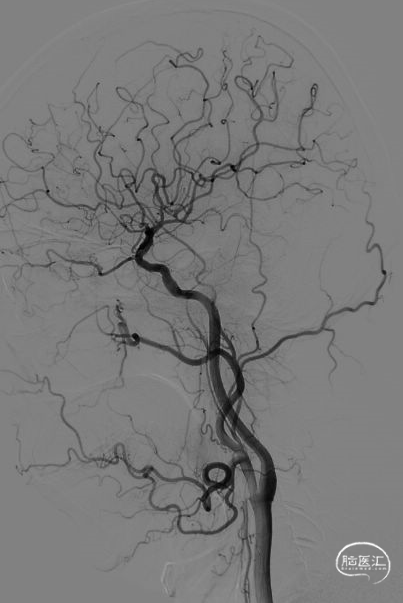

将2.0x9mm SacSpeed®球囊扩张导管沿微导丝送至右侧大脑中动脉M1段狭窄处由远及近分别给予7、7.5、8个大气压由远及近依次扩张,每次扩张后予以欣维宁2ml缓慢静推,扩张结束后造影显示右侧大脑中动脉狭窄处较前明显改善,残余狭窄<30%,TICI分级2b级以上。

术后2小时拔除动脉鞘,拔出动脉鞘后给予压迫器压迫止血。右下肢24小时保持伸直状态,穿刺部位敷贴包扎。术后拟复查头颅CT,行心电监测,收缩压控制在90-110mmHg,予甘露醇静滴脱水,甲强龙静滴促进造影剂排泄,欣维宁静脉泵入6ml/h维持4h,5ml/h维持4h,4ml/h维持至术后72h,密切观察患者意识、精神状态,观察局部有无血肿、出血,使用必要的抗生素。

复查头颈部CTA:右大脑中动脉M1-3段粗细不均,M1段局部重度狭窄。